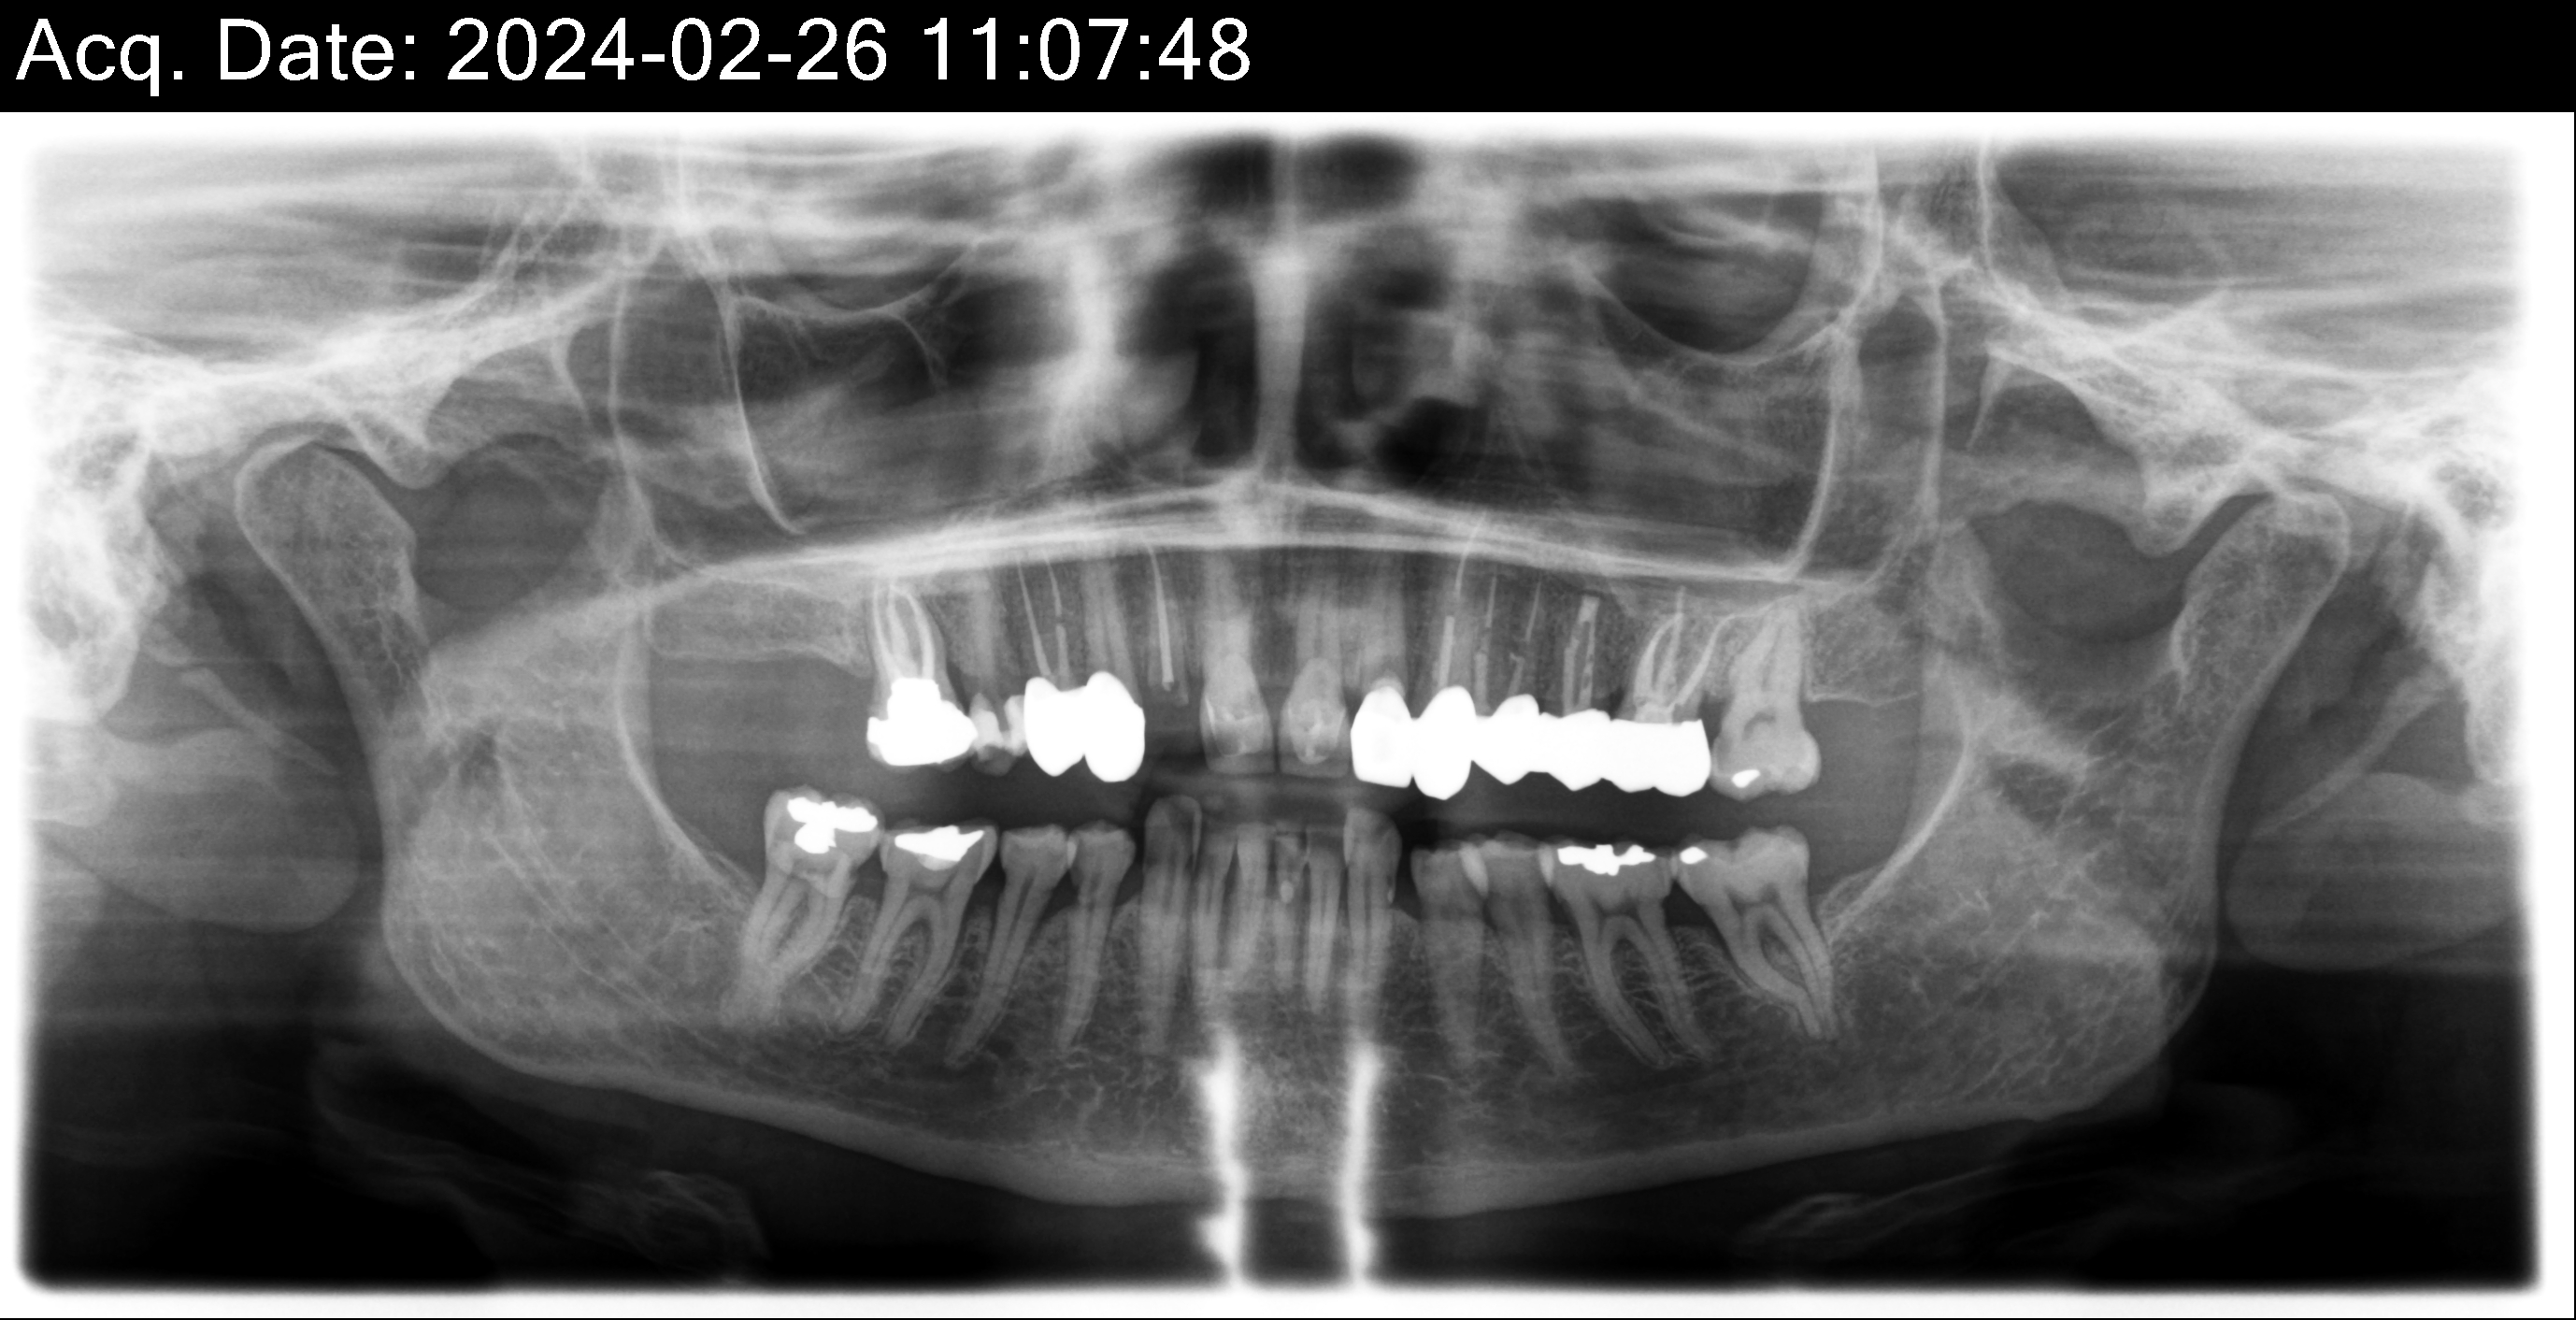

Dental Auction No. 11561: Several extractions and All-on-4 Top and bottom arches

| Restorative | HY | HY | HY | HY | HY | HY | HY | HY | HY | HY | HY | HY | HY | HY | ||

| Surgical | X | X | X/IMP | X | X/IMP | X | X | X | X/IMP | X | X/IMP | X | X | X | ||

| Current situation | x | c | c | c | c | x | x | c | c | x | x | c | c | c | x | x |

| Tooth # | 1 | 2 | 3 | 4 | 5 | 6 | 7 | 8 | 9 | 10 | 11 | 12 | 13 | 14 | 15 | 16 |

| Tooth # | 32 | 31 | 30 | 29 | 28 | 27 | 26 | 25 | 24 | 23 | 22 | 21 | 20 | 19 | 18 | 17 |

| Current situation | x | c | c | x | ||||||||||||

| Restorative | HY | HY | HY | HY | HY | HY | HY | HY | HY | HY | HY | HY | HY | HY |

12,13,14 have had root canals in past and now have quite a bit movement. 2-5 have all had root canals in past and now the crowns are breaking down.

Overall, all of my gums have receded and most of the bottom teeth are exposed w/ some roots and there are many cavities.